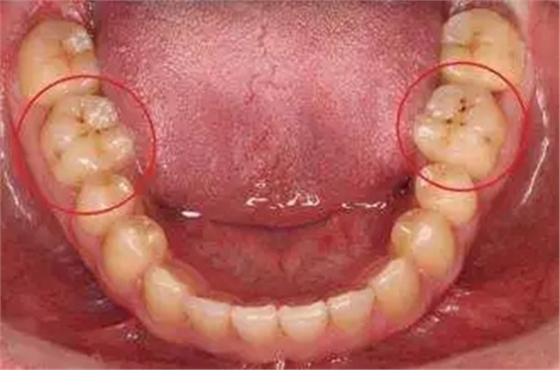

早上刷牙發(fā)現(xiàn)里面的大牙有黑線的情況,一開(kāi)始我們都會(huì)以為可能是食物臟東西殘留在牙齒上,用水漱口就可以清潔掉了。但是,當(dāng)我們用刷牙清潔、漱口都無(wú)法清除黑線的時(shí)候,我們就要引起警惕了。因?yàn)檫@種情況下,我們的牙齒已經(jīng)開(kāi)始齲蛀了。

1、牙齒表面形成黑線,也就是窩溝齲,這是初步形成的蛀牙。